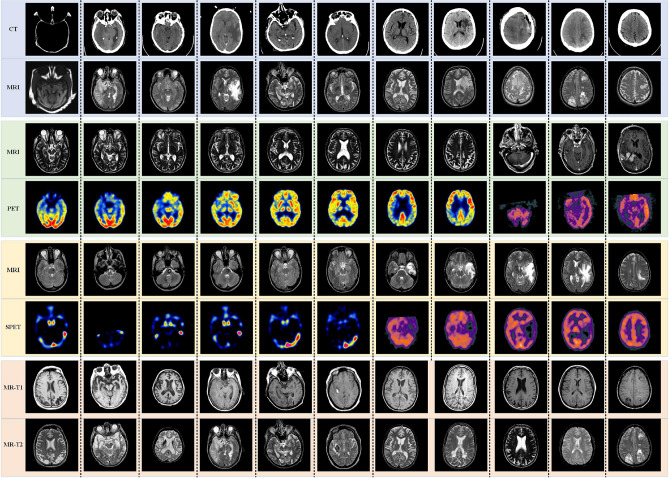

In our experiment, 44 pairs of multi-modal medical images, i.e. CT and MRI, MRI and PET, MRI and SPECT, MR-T1 and MR-T2, are adopted as experimental datasets. Figure 2 shows the original images, which have been accurately registered before fusion. The size of each source image is 256 * 256 pixels.

Figure 2.

44 pairs of multi-modal medical images.